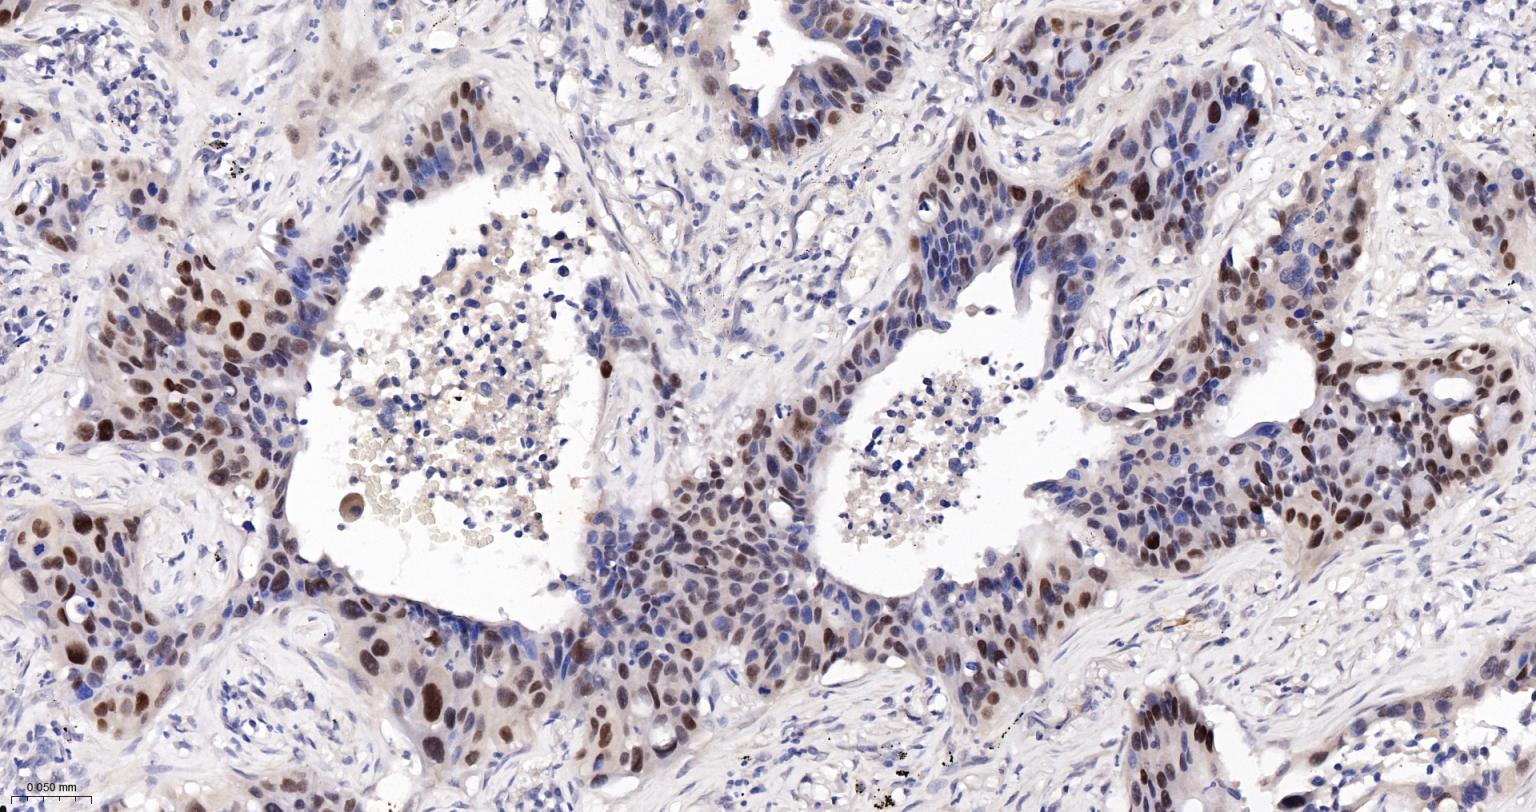

Paraformaldehyde-fixed, paraffin embedded Human Gastric Cancer; Antigen retrieval by boiling in sodium citrate buffer (pH6.0) for 15 min; The section was incubated with P53 Monoclonal Antibody, Unconjugated (bsm-33058M) at 1:600 overnight at 4°C, followed by conjugation to the bs-40296G-HRP and DAB (C-0010) staining.